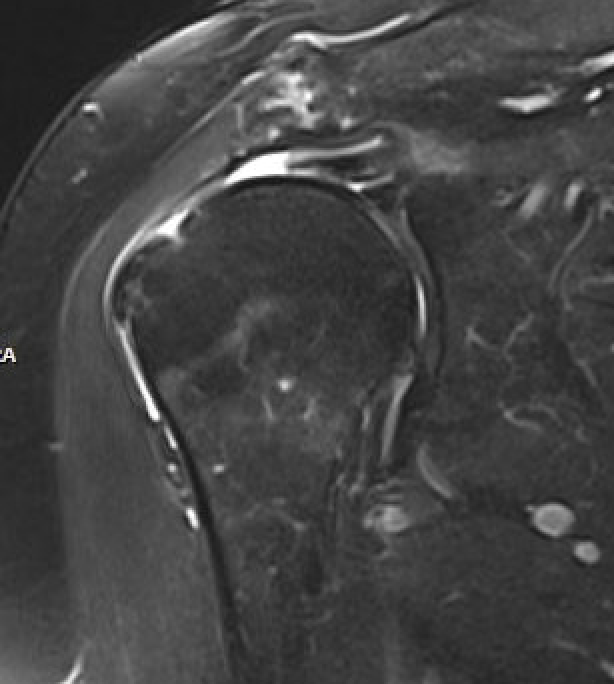

MRI

Look for

- supraspinatus / infraspinatus / subscapularis / long head of biceps pathology

- partial verus full thickness

- size of tear in coronal and sagittal planes

- retraction

- atrophy / fatty infiltration

Full thickness rotator cuff tears

Partial bursal sided tear Partial articular sided tears